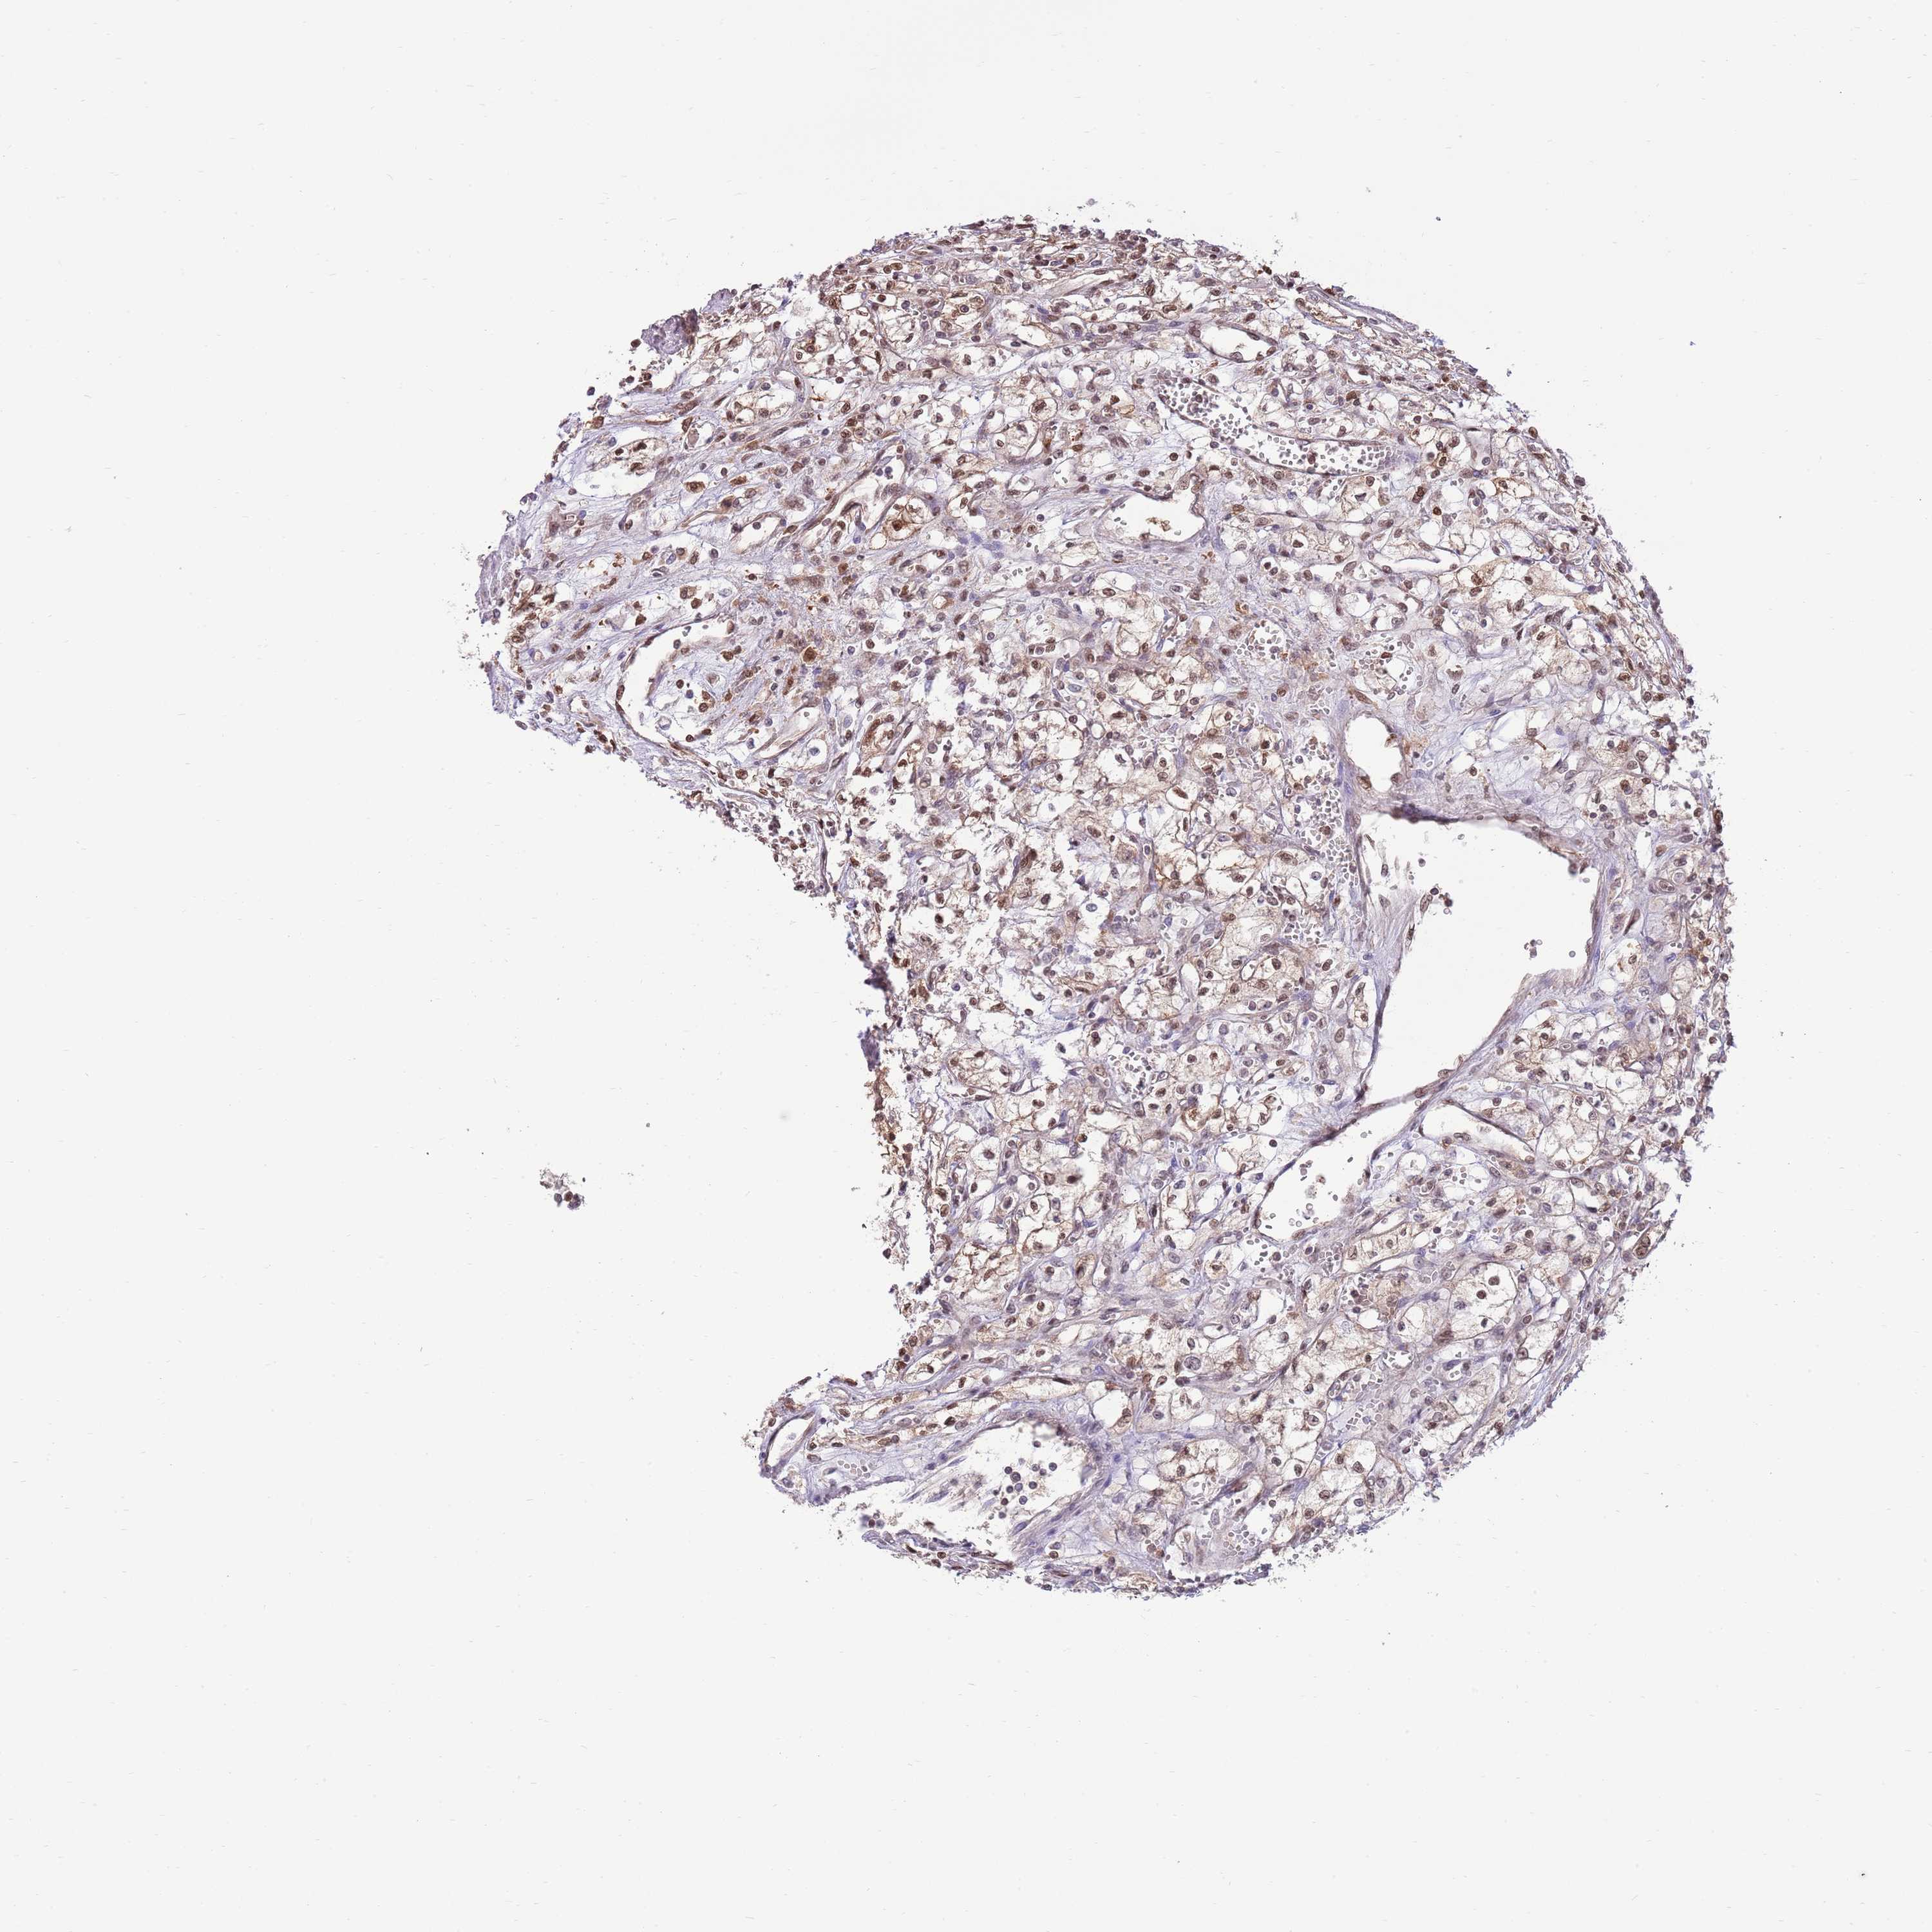

KIDNEY RENAL CLEAR CELL CARCINOMA (VALIDATION) - Interactive survival scatter ploti

The Survival Scatter plot shows the clinical status (i.e. dead or alive) for all individuals in the patient cohort, based on the same data that underlies the corresponding Kaplan-Meier plots. Patients that are alive at last time for follow-up are shown in blue and patients who have died during the study are shown in red.

The x-axis shows the expression levels (FPKM) of the investigated gene in the tumor tissue at the time of diagnosis. The y-axis shows the follow-up time after diagnosis (years). Both axes are complimented with kernel density curves demonstrating the data density over the axes. The top density plot shows the expression levels (FPKM) distribution among dead (red) and alive patients (blue). The right density plot shows the data density of the survived years of dead patients with high and low expression levels respectively, stratified using the cutoff indicated by the vertical dashed line through the Survival Scatter plot. This cutoff is automatically defined based on the FPKM cutoff that minimizes the p-score. The cutoff can be changed by dragging the vertical line or by entering a cutoff value in the square labeled "Current cut-off".

Under the Survival Scatter plot the p-score landscape (black curve; left axis) is shown together with dead median separation (red curve; right axis). Dead median separation is the difference in median mRNA expression between patients who have died with high and low expression, respectively. It is calculated as follows: median FPKM expression of dead patients with high expression - median FPKM expression of dead patients with low expression. This is intended to aid the user in visually exploring custom cutoffs and the associated p-scores and dead median separation.

Individual patient data is displayed and can be filtered by clicking on one or more of the category buttons on the top of the page. Categories describing expression level and patient information include: high, low, alive, dead, female, male and tumor stages. The scale of the x-axis can be toggled between linear and log-scale by clicking on the "x log" button. Mouse-over function shows TCGA ID, patient information and mRNA expression (FPKM) for each patient.

& Survival analysisi

Kaplan-Meier plots summarize results from analysis of correlation between mRNA expression level and patient survival. Patients were divided based on level of expression into one of the two groups "low" (under cut off) or "high" (over cut off). X-axis shows time for survival (years) and y-axis shows the probability of survival, where 1.0 corresponds to 100 percent.

NSFL1C is not prognostic in Kidney Renal Clear Cell Carcinoma (validation)

: 32.74

Average pTPM 29.2

Number of samples 100